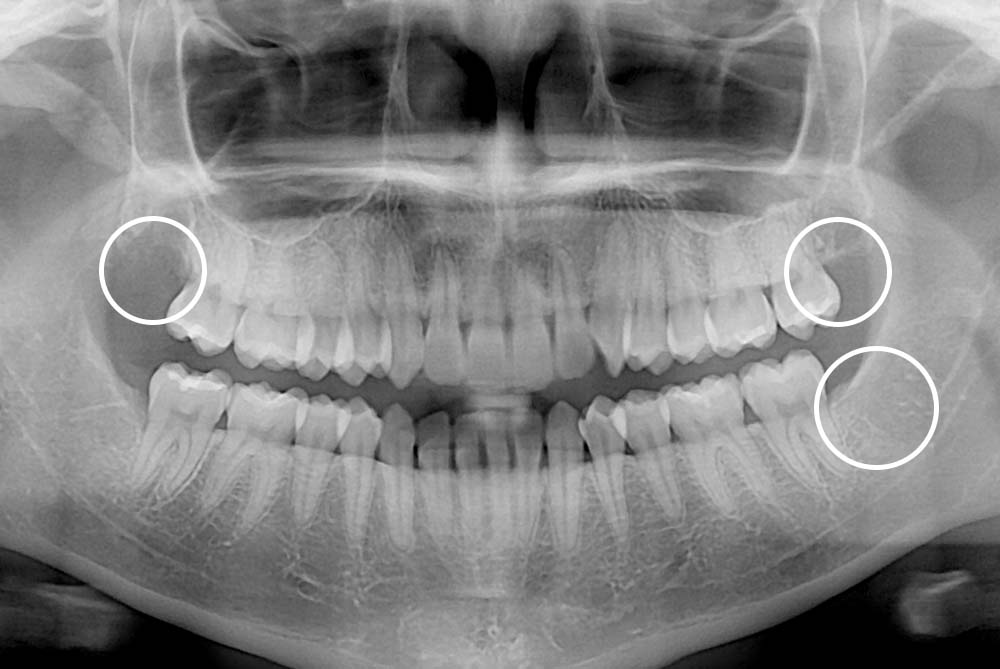

치료사례

세종치과의 진심 어린 치료는 결과로 말합니다.

실제 내원하신 환자분들의 치료 전·후 사례를 확인해보세요.

모든 치료사례 전후사진은 환자분의 동의하에 촬영되었습니다.

모든사진은 동일 환자분의 전후모습을 촬영하였으며, 사진의 밝기조절 외에 임의 수정이 없음을 알려드립니다.